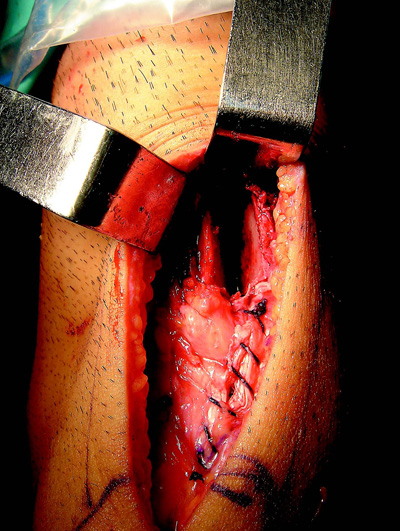

- Cierre en flexión del tendón rotuliano y del peritendón.

- Relleno del lecho del injerto con injerto óseo extraído de túneles preferentemente tibial, que se realiza durante el fresado del túnel. (Figs. 1 y 2).

Figura 1: Lecho de cosecha de injerto de bloque óseo patelar. |

Figura 2: Colocación de injerto óseo en lecho de cosecha de injerto en la patela. |